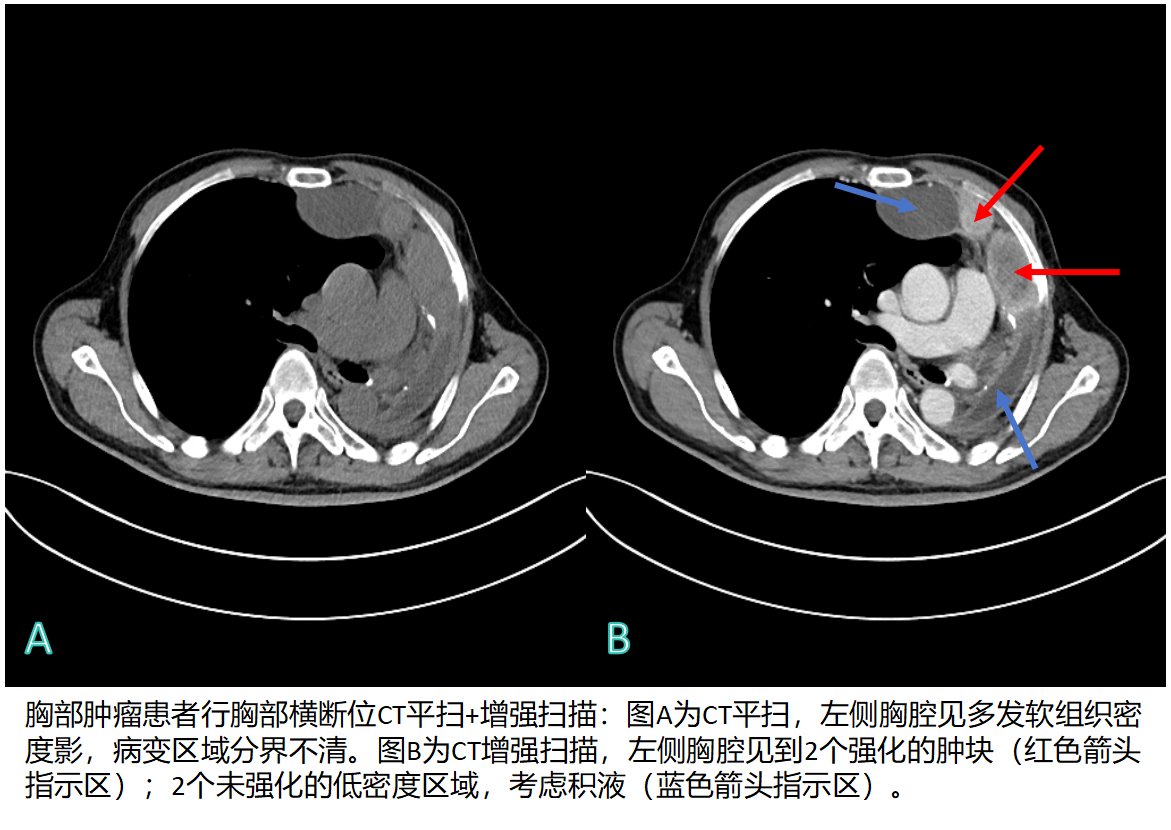

3126217f4856f202872ff4123ff3f037.png